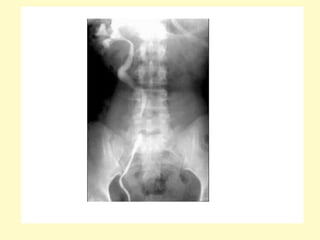

Intravenous urogram showing right-sided hydronephrosis and the

dilation of the proximal ureter up to the level of the L3 transverse

process, the medial deviation of the ureter at this level (arrow) gives

rise to the typical fish hook or reversed S appearance